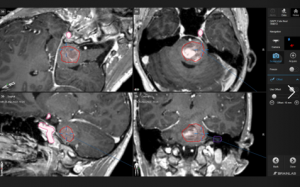

Bei einem Akustikusneurinom muss immer eine ausführliche neuroradiologische Bildgebung in einem MRT („Röhre“) durchgeführt werden. Es werden Dünnschicht-MRT-Bilder (mit 1 mm oder weniger Schichtdicke mit Kontrastmittel-, Nativ- und T2- sowie CISS-Spezialsequenzen) zur Darstellung der Hirnnerven mit unterschiedlichen Hervorhebungen benötigt. Zudem wird zur Einschätzung der knöchernen Verhältnisse ein dünnschichtiges CT der Schädelbasis und des Felsenbeins (ein Abschnitt des Schläfenbeins) durchgeführt.

Die Abbildung zeigt die Planung zur Entfernung eines Cavernoms des Hirnstamms mit Hilfe der Augmented Reality und die intraoperative Darstellung. Das Cavernom konnte komplett entfernt. Die durch die Blutung entstandenen neurologischen Ausfälle haben sich nach der Operation komplett zurückgebildet.